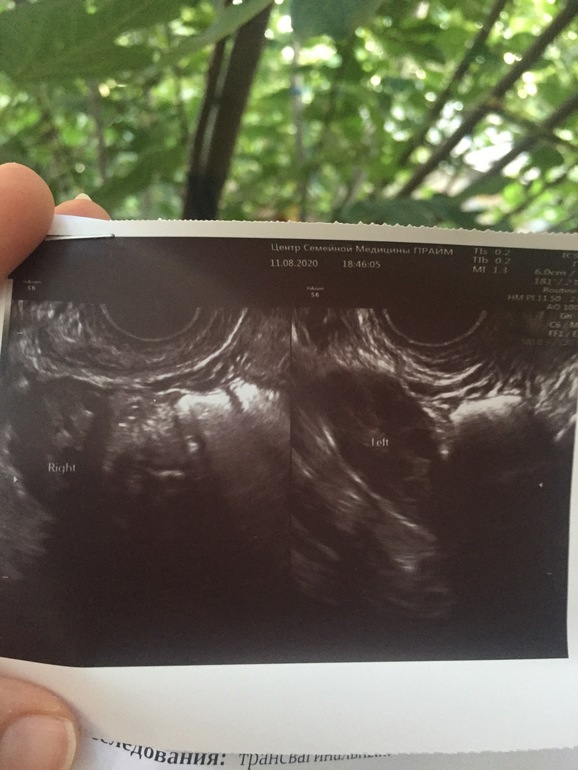

ФолликулометрияУЗИ на 17д. ц., была ли О? И может ли быть в этом месяце? Первый месяц отмены Ок. Цикл 25-28 дней. Спасибо.

Для 17дц картина свидетельствует об ановуляторном цикле, либо овуляция была совсем недавно (свободная жидкость в малом тазу скорее всего как следствие недавней овуляции, но надо в динамике смотреть). Мультифолликулярные яичники. Правый ещё и увеличен немного, наверное, поликистоз ещё можно заподозрить,либо овуляция была в нём и где то там прячется желтое тело. Ничего криминального нет :)